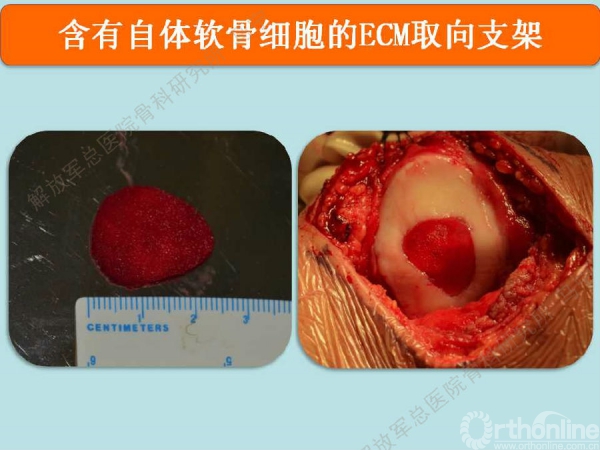

上图是我们院自主研发的以软骨细胞外基质为原料的孔隙取向性支架。可以做成任意厚度任意大小,按照软骨缺损的形状裁剪好以后。这个损伤面积大概在4平方厘米左右。